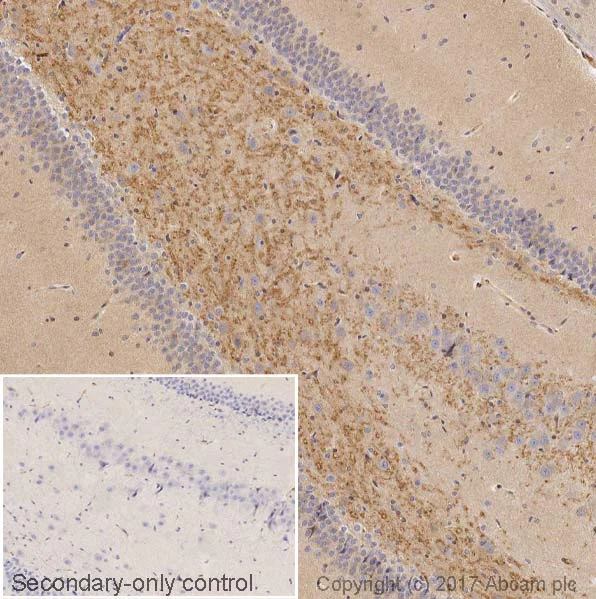

Immunohistochemistry (Formalin/PFA-fixed paraffin-embedded sections) - Anti-BDNF antibody [EPR21211] (AB213323)

IHC image of BDNF staining in normal rat brain dentate gyrus formalin fixed paraffin embedded tissue section, performed on a Leica BondTM system using the standard protocol B. The section was pre-treated using heat mediated antigen retrieval with sodium citrate buffer (pH6, epitope retrieval solution 1) for 20 mins. The section was then incubated with ab213323, 0.05 μg/ml, for 15 mins at room temperature. A goat anti-rabbit biotinylated secondary antibody was used to detect the primary, and visualized using an HRP conjugated ABC system. DAB was used as the chromogen. The section was then counterstained with haematoxylin and mounted with DPX. The inset secondary-only control image is taken from an identical assay without primary antibody.

For other IHC staining systems (automated and non-automated) customers should optimize variable parameters such as antigen retrieval conditions, primary antibody concentration and antibody incubation times.